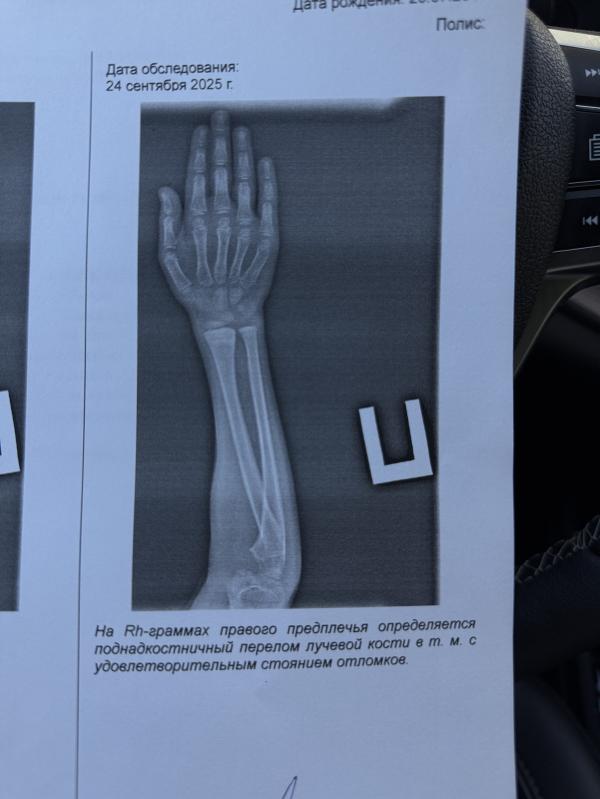

Девочки, кто разбирается скажите пожалуйста, так и остался перелом у нас, верно?

Врач принимал, сколько по времени носите гипс? Нам перед тем аак снять, тоже в снимке было написано удовлетворительное состояние. Носил гипс 4 недели точно

@yaninalats, у нас костная ткань наросла, но еще не закрепилась чтоб 200%. Если б все ок было, то она скашала было б написано перелома нет.